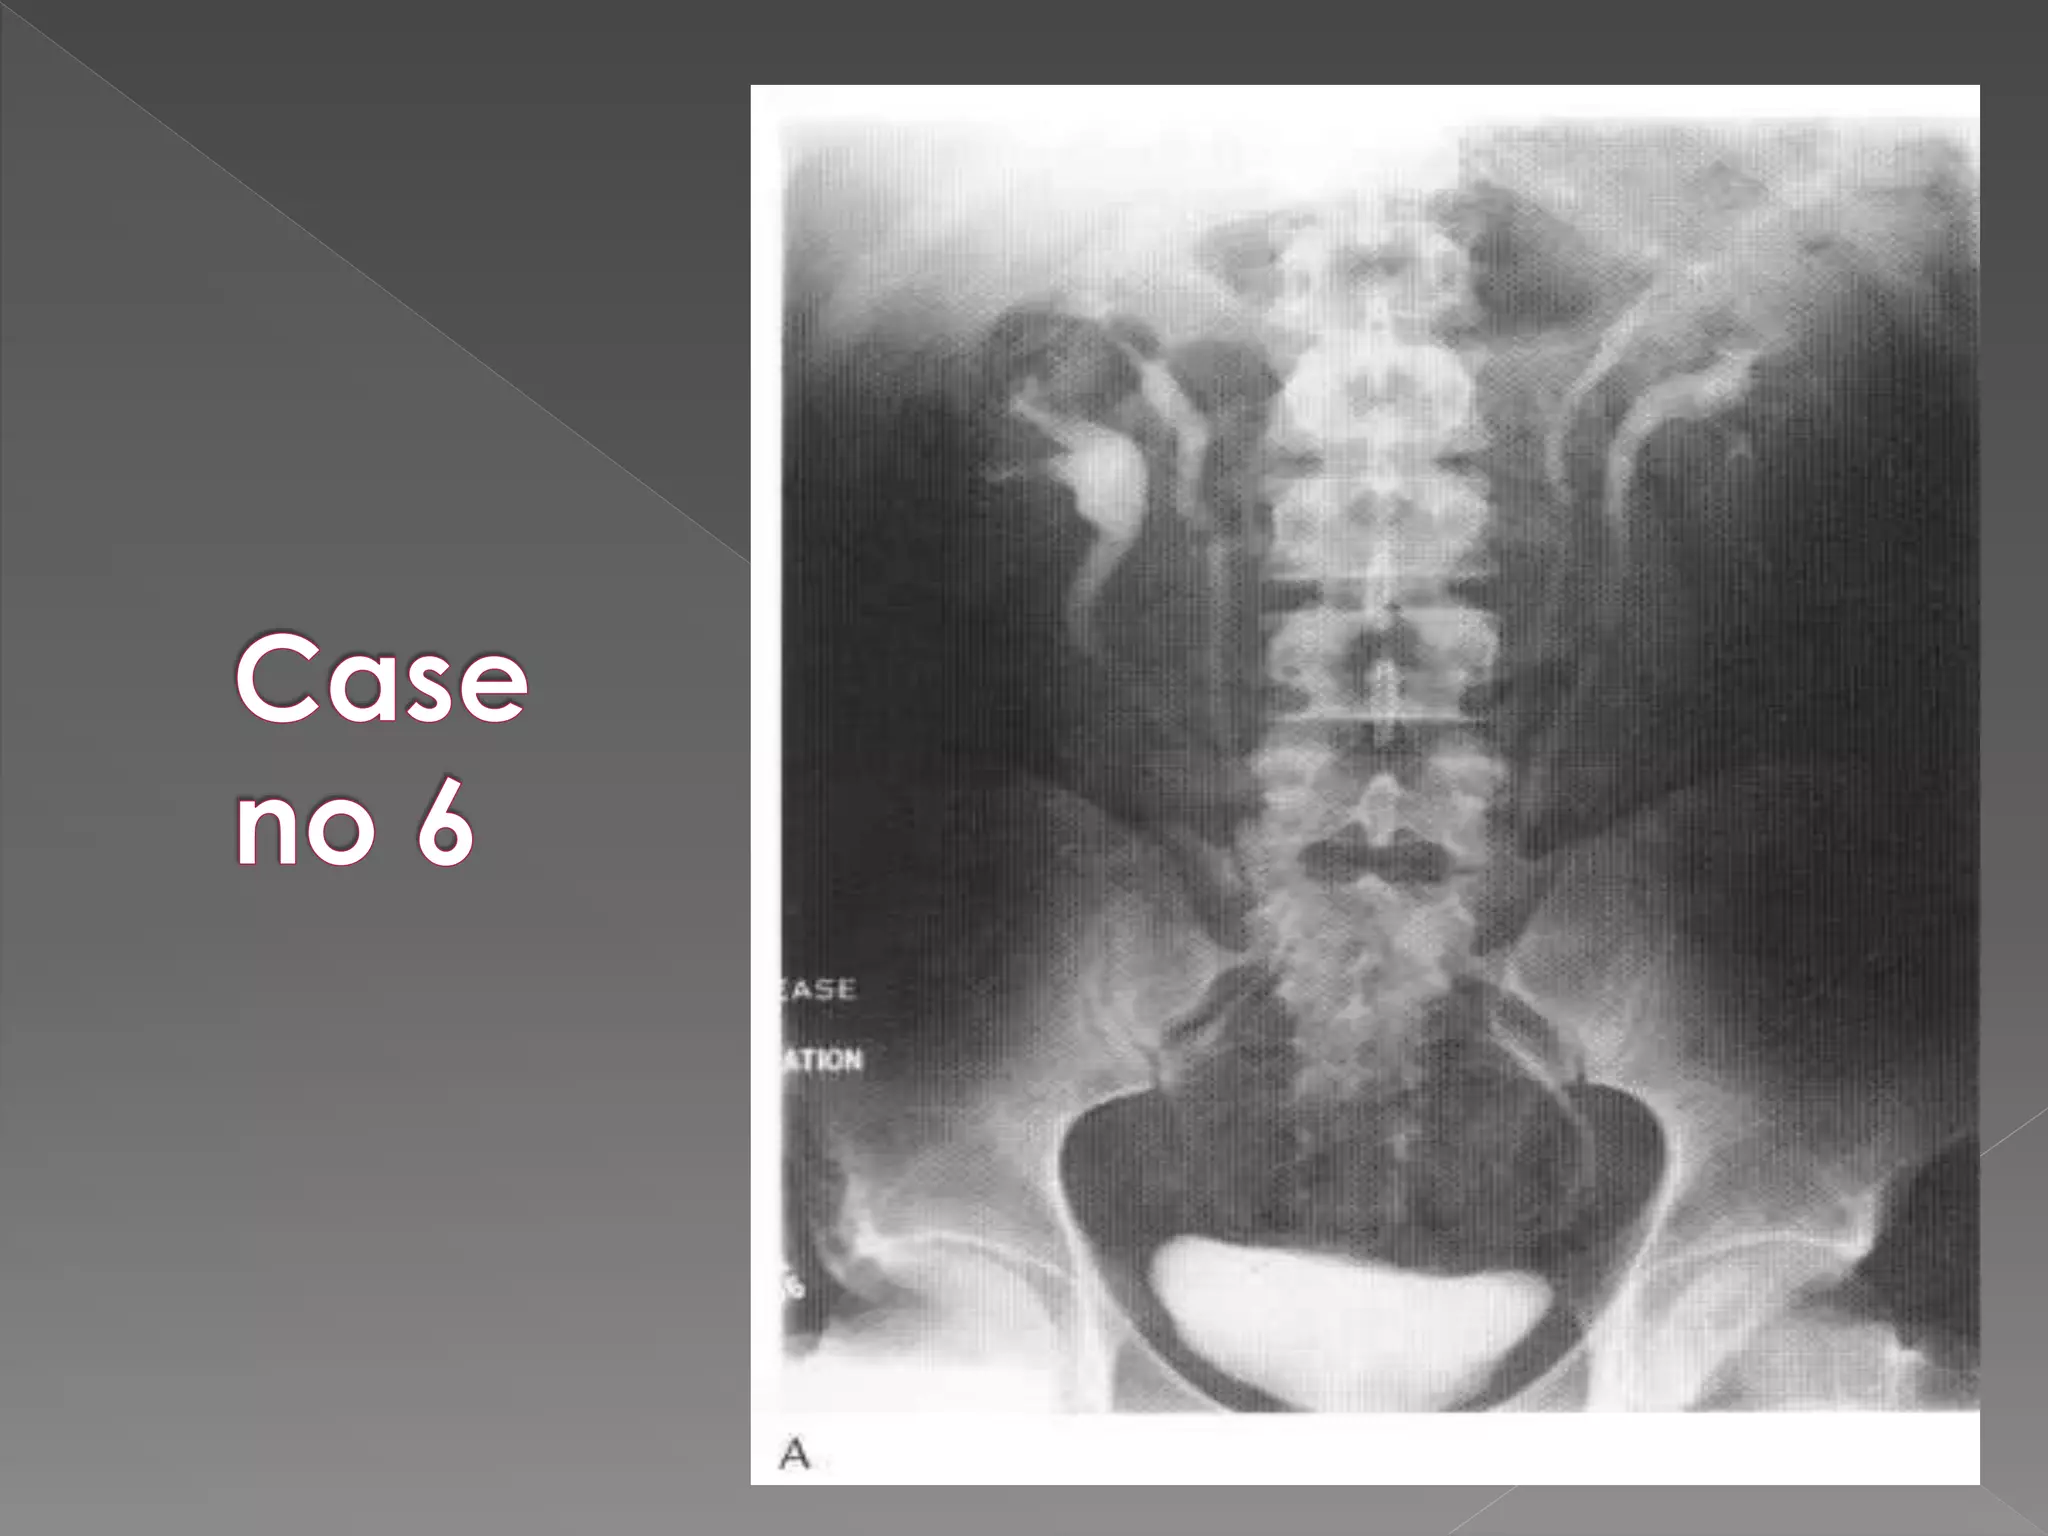

 Contrast takes12-20 sec to reach the renal arteries after iv injection.  Nephrogram : diffuse enhancement which healthy kidneys show In the 1st min of IVU.  Renal size 3-4 vertebrae in length no > 4 vertebrae  Out lines best seen in 1st 30 sec.

 Medullary orpyramidal blush:  Contrast may be visible as fine linear opacities running along the medullary pyramids  Pyelogram:  Excretion of contrast into the pelvis & ureter  Compression impedes ureteric drainage & distends PCS at12-15 mins

 On releasingcompression increase flow in ureters making them prominent in post release film.  Normal ureters have contractions & are not seen entire length.  There are smoothly narrowed areas esp at PUJ and as the ureters cross ilial vessels in pelvis.